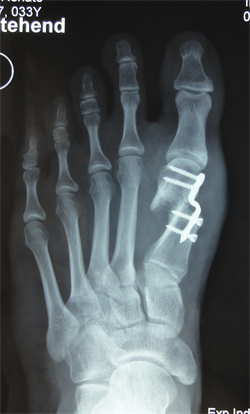

Figure 7. Patient Nr. 2. Hallux valgus with subluxed Ist MPJ and pathological DMAA.

Figure 8. Patient Nr. 2: Correction with 100% lateralization and only point contact of the osteotomy partners.

Figure 9. Patient Nr. 2. Result after 7 years. All components are corrected, no loss of lenght. Immediate full weight bearing, running after 8 weeks.